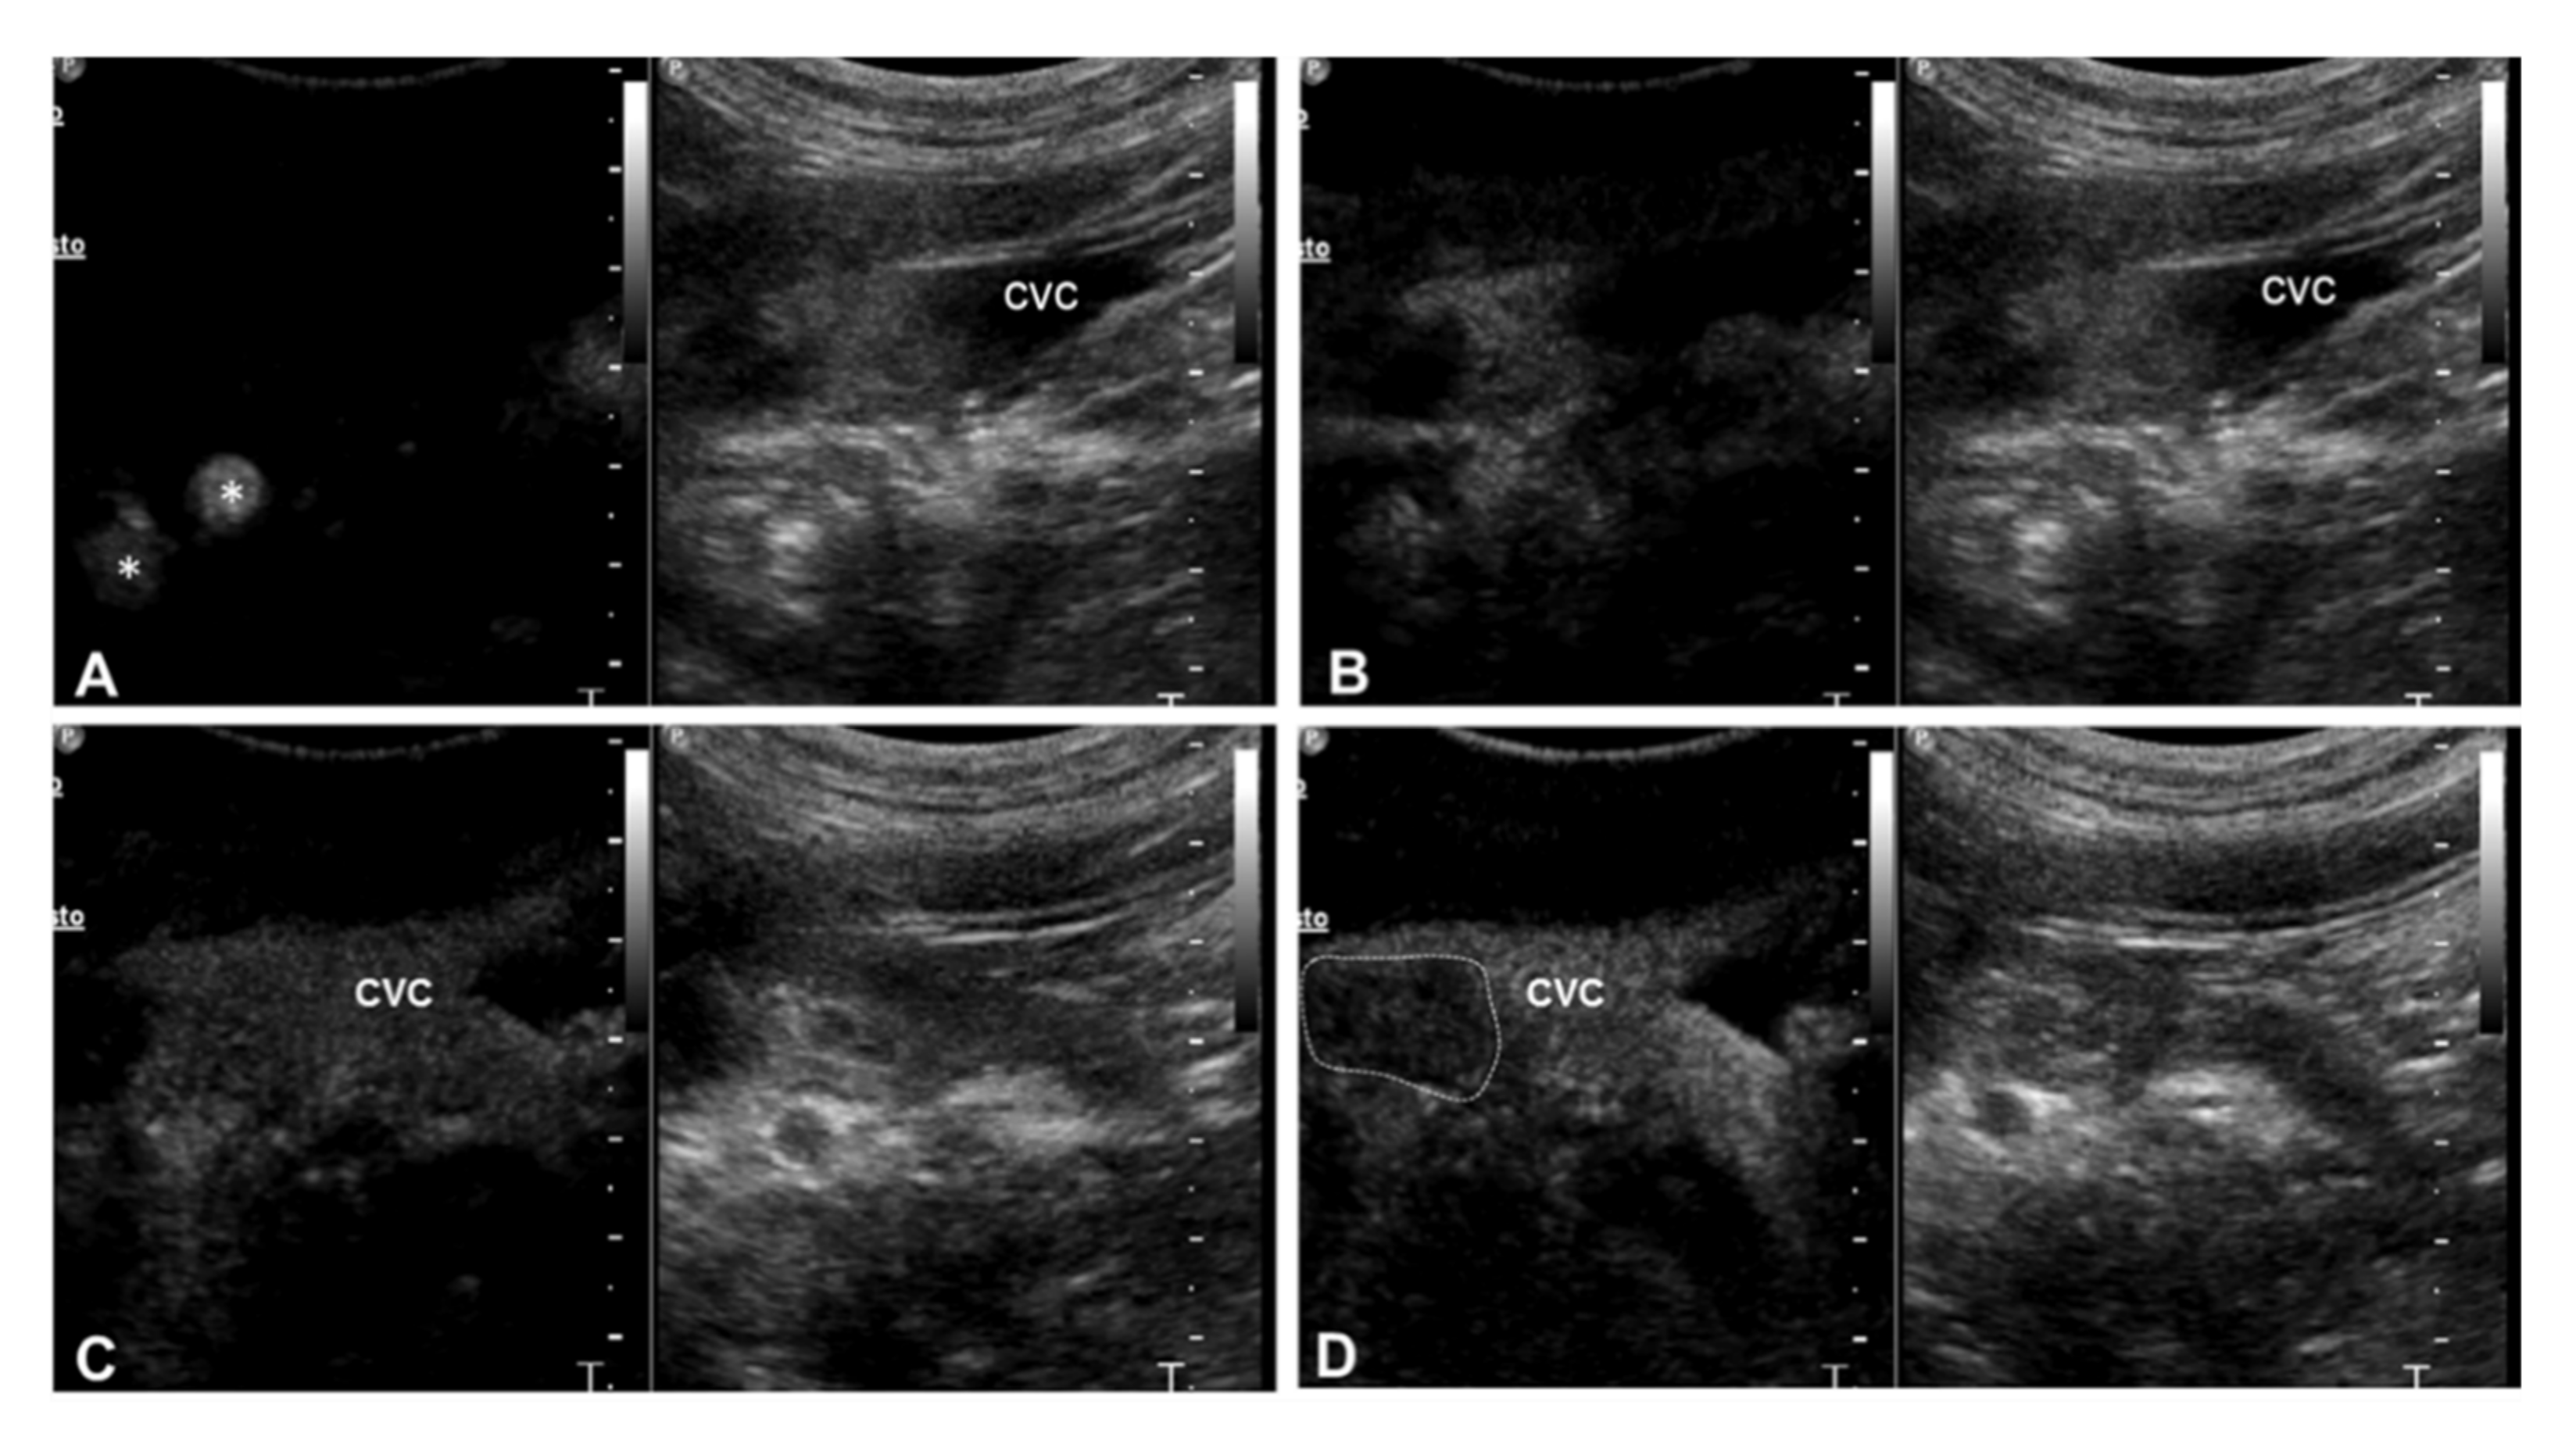

| 3 | Right adrenal carcinoma | Caudal vena cava | 1 Heterogeneous partially hyperechoic nodule with acoustic shadowing on the right adrenal gland (2.9 cm) | Intravascular homogeneous mass in contiguity with the primary tumor | Residual flow within the lumen of the vessel | Present | Heterogeneous | Irregular and ill-defined | Earlier | N/A |

| 4 | Right adrenal carcinoma | Caudal vena cava | Heterogeneous partially hyperechoic right adrenal gland with acoustic shadowing (width 1.5 cm) | Intravascular homogeneous mass with vessel distension | Residual flow within the lumen of the vessel | Present | Heterogeneous | Irregular and ill-defined | Earlier | N/A |

| 6 | Left adrenal pheochromocytoma | Caudal vena cava | Heterogeneous left adrenal gland (width 2.3 cm) | Intravascular homogeneous mass with vessel distension | Residual flow within the lumen of the vessel | Present | Heterogeneous | Irregular and ill-defined | Earlier | N/A |

| 7 | Retroperitoneal liposarcoma | Caudal vena cava | Heterogeneous mass on the left retroperitoneal space, involving the left adrenal gland (3.5 cm) | Intravascular homogeneous mass | Intralesional Doppler signal; residual flow within the lumen of the vessel | Present | Heterogeneous | Irregular and ill-defined | Earlier | NA |